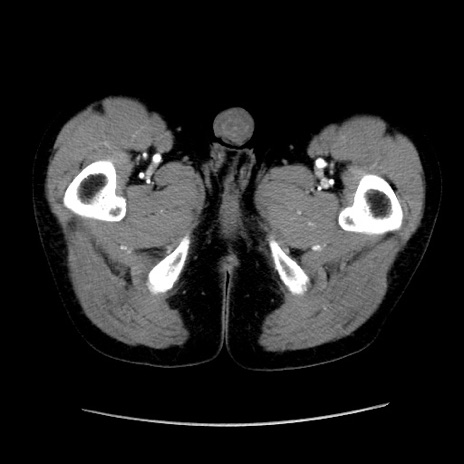

症例37(横断像)

【症例】40歳代 男性

【主訴】腹痛

【現病歴】4時間ほど前に電車に乗車中に臍部上より腹痛出現。徐々に増悪し起立困難となり、救急外来受診。生ものは数日食べていない。今朝お雑煮を食べた。

【身体所見】BT 36.8℃、BP 117/84mmHg、HR 91/min、SpO2 97%、苦悶様、腹部:臍上部広範囲圧痛あり、反跳痛±

【データ】WBC 8100、CRP 0.03